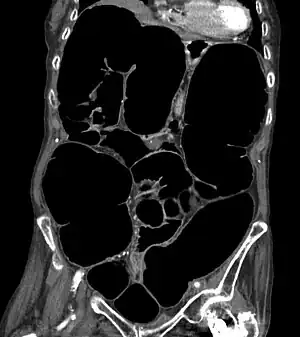

CT scan of the abdomen of an elderly woman with Ogilvie syndrome

It generally occurs in those with significant health problems or following surgery.[2][1] While the underlying mechanism is unclear, it is believed to involve poor contraction of the colon.[3][1] Generally the cecum has a diameter of more than 10 cm and right colon is also dilated.[4] A CT scan or water-soluble enema is done to rule out a obstruction.[1]